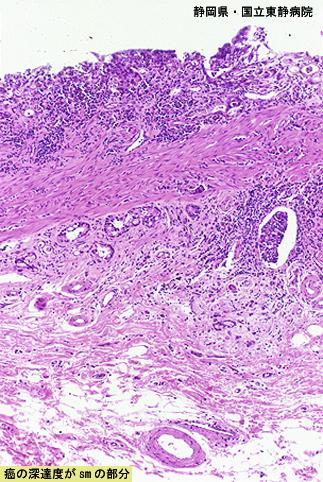

疾病(病理主体)的分类恶性上皮性肿瘤/印戒细胞癌

检查方法病理切片(微观)